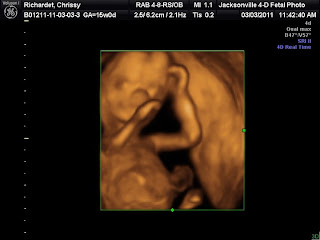

It's a Boy!

Sorry for the late news which most of you know about! We went 3 weeks ago and had a 3d/4d ultrasound done to find out the sex of our newest little edition. We both had our feelings that it was a girl. However we were wrong! So in just a few more months we will be welcoming our little Timothy James Richardet.

Little Timmy as Miss Hailey calls him is due on his big brothers birthday, so he will be able to wear everything we have kept from when Nick was a tiny baby. Not to mention a great friend of mine gave me all her sons clothes so they should fit during the seasons also since our big boys are only month apart! Of course he will have new things though, you all know me too well for that! We already have some hospital outfits picked out and will be getting them shortly!